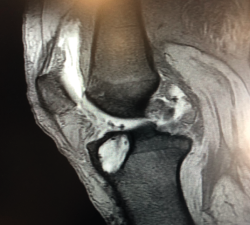

Figura 1. Laxitud en el cajón anterior. Radiología forzada.

Desde el punto de vista clínico, se consideran motivo de revisión quirúrgica aquellos casos en los que exista un desplazamiento anterior comparado con el contralateral mayor de 5 mm, pivot shift de alto grado, dolor, inflamación, sensación subjetiva de inestabilidad y limitación funcional para las actividades de la vida diaria o deportiva(9,10). Algunos autores han rebajado esta cifra a 3 mm con respecto a la rodilla contralateral o 10 mm de desplazamiento absoluto en el plano sagital(11)(Figura 1).